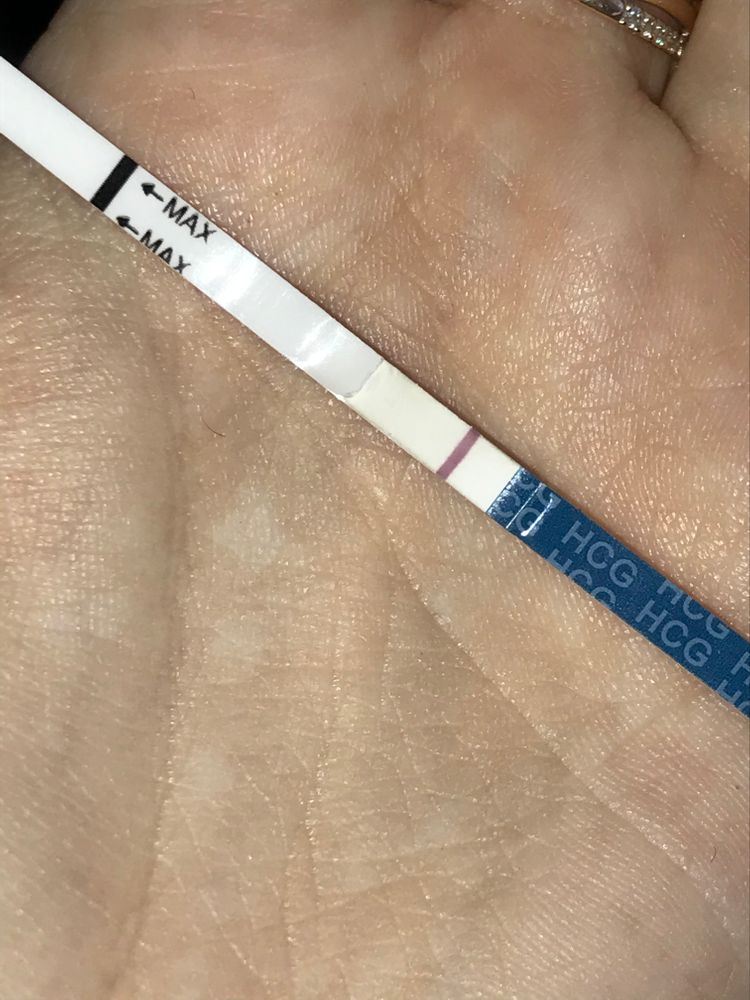

Что видите ?

Вчера закончились месячные,но были подозрения и решила сделать тест.

Вижу только одну,а вы ?

Вчера закончились месячные,но были подозрения и решила сделать тест.

Вижу только одну,а вы ?

Девочки,что видите вы ? Видим плюс или кажется ?